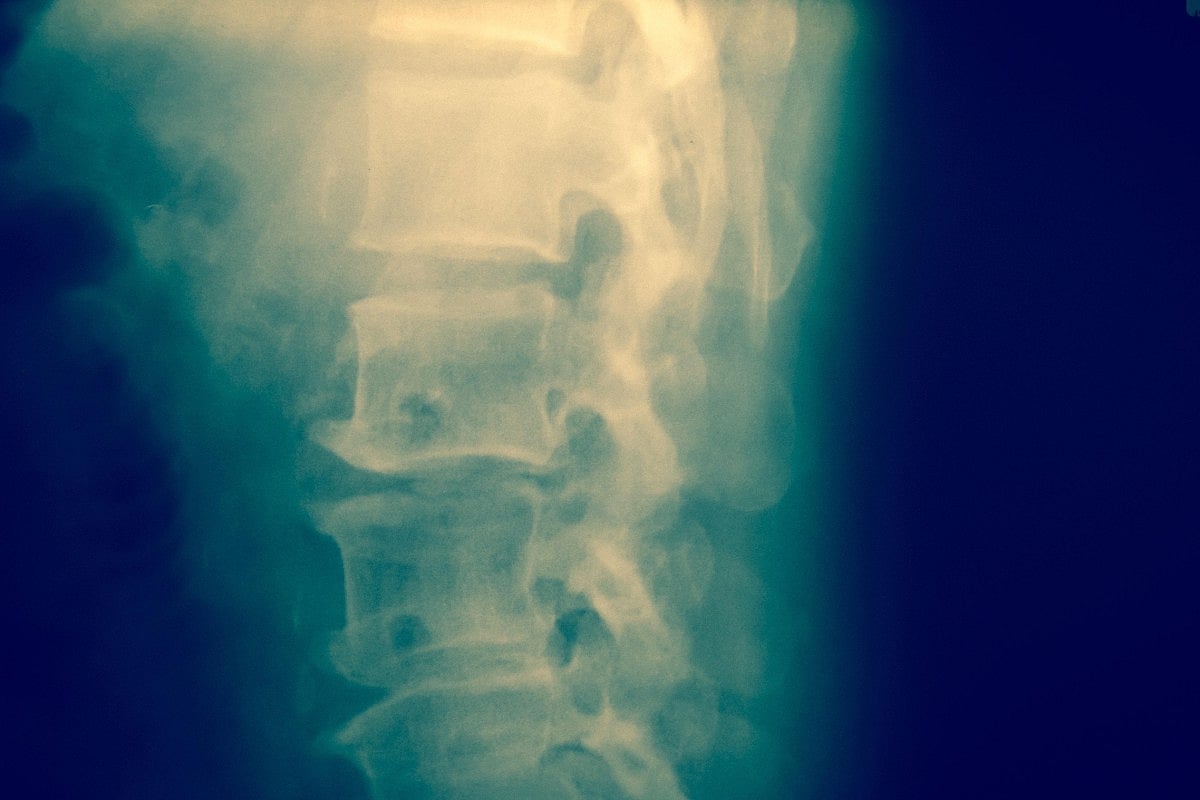

MONDAY, May 20, 2025 (HealthDay News) — A brain wave decoder shows promise in using electrical stimulation to the spine to cue leg movement, researchers say.

The decoder could one day help restore mobility in people with spinal cord injuries.

Tests in 17 people without a spinal cord injury showed that the decoder could cue movement in their lower legs using spinal cord stimulation, researchers reported in the Journal of NeuroEngineering and Rehabilitation.

Using those brain waves, people were able to move their lower leg by just thinking about it, with an external electrode stimulating their spinal cord into producing the movement, researchers reported.

The study is a first step toward developing a brain-spine interface that uses real-time brain waves and spinal cord stimulation to promote movement in people with a spinal cord injury, researchers said.